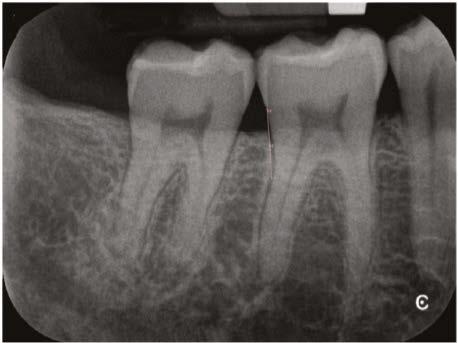

One of the most critical steps in treating dental trauma is making sure you don’t rush things. That means that obturation is often postponed until the patient is asymptomatic (i.e., no pain to percussion) and the periodontal ligament has radiographically re-established itself. Clinicians must also make sure the tooth is completely disinfected of bacteria. Both of these steps are achieved by placing calcium hydroxide as an intracanal medicament during the treatment as seen in Figure 4.

From here (Figure 6), I could see that my gutta percha was slightly overextended so I trimmed my master cones a bit prior to permanently obturating the teeth here.

Figure 5

There was some sealer extrusion at the apex of these teeth (Figure 7), especially 10, but this was due to the inflammatory resorption occurring at the apex as a result of the trauma, which started to eat away the apical stop. I am confident that, over time, this sealer will resorb away, and this extrusion should not impede the healing at all. Figure 8 is the final outcome of the case.